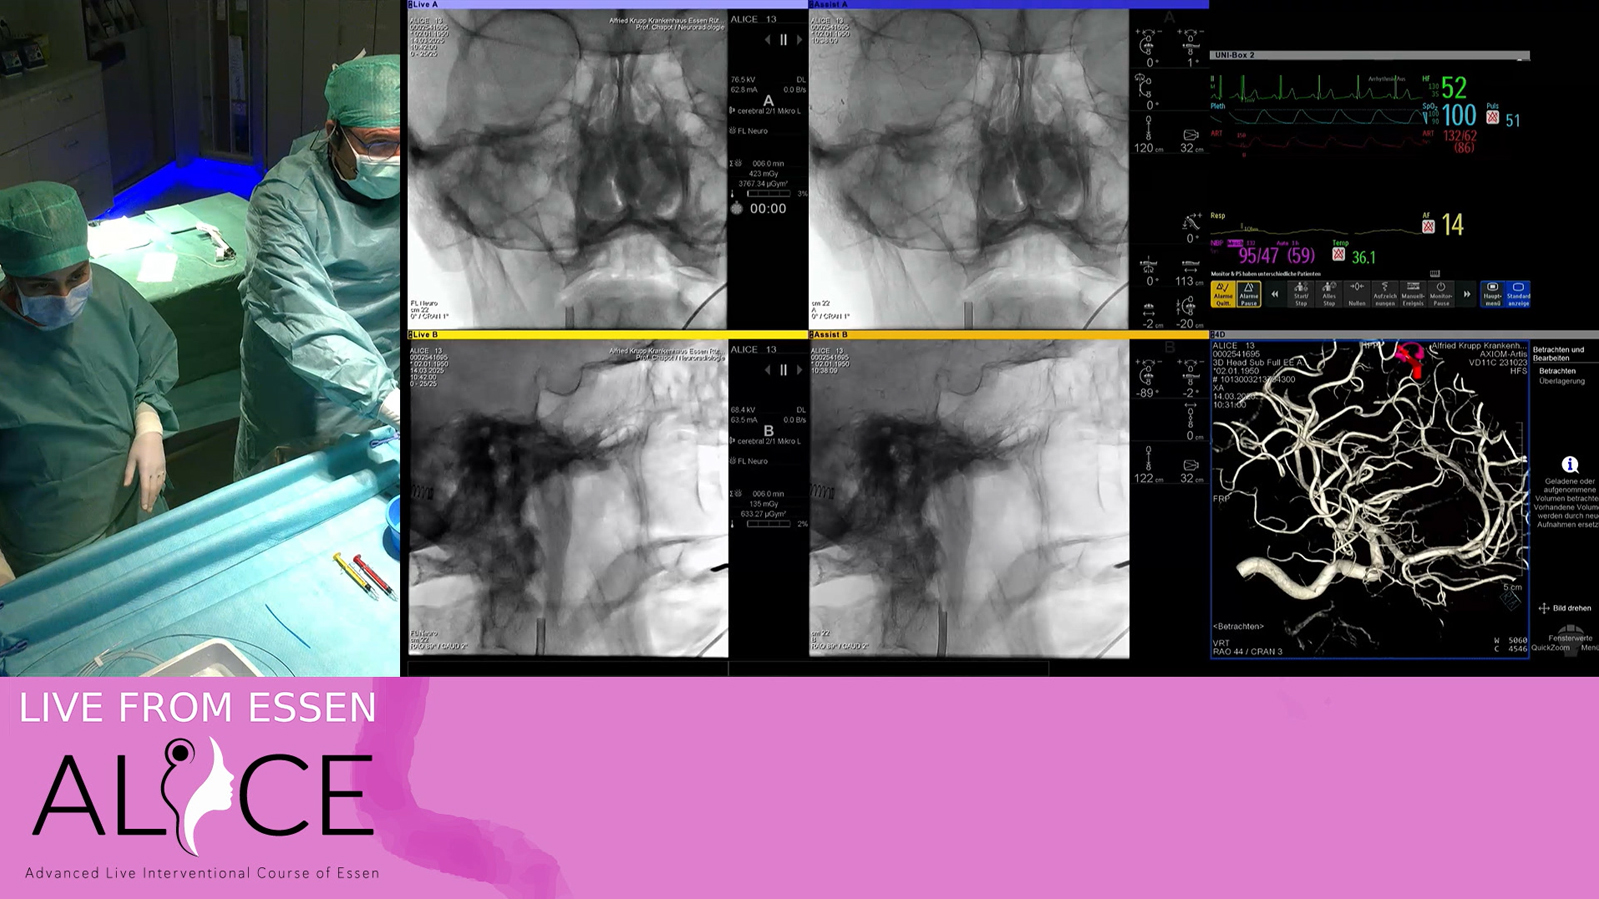

Ruptured hypothalamic AVM treated by transarterial embolization with PHIL